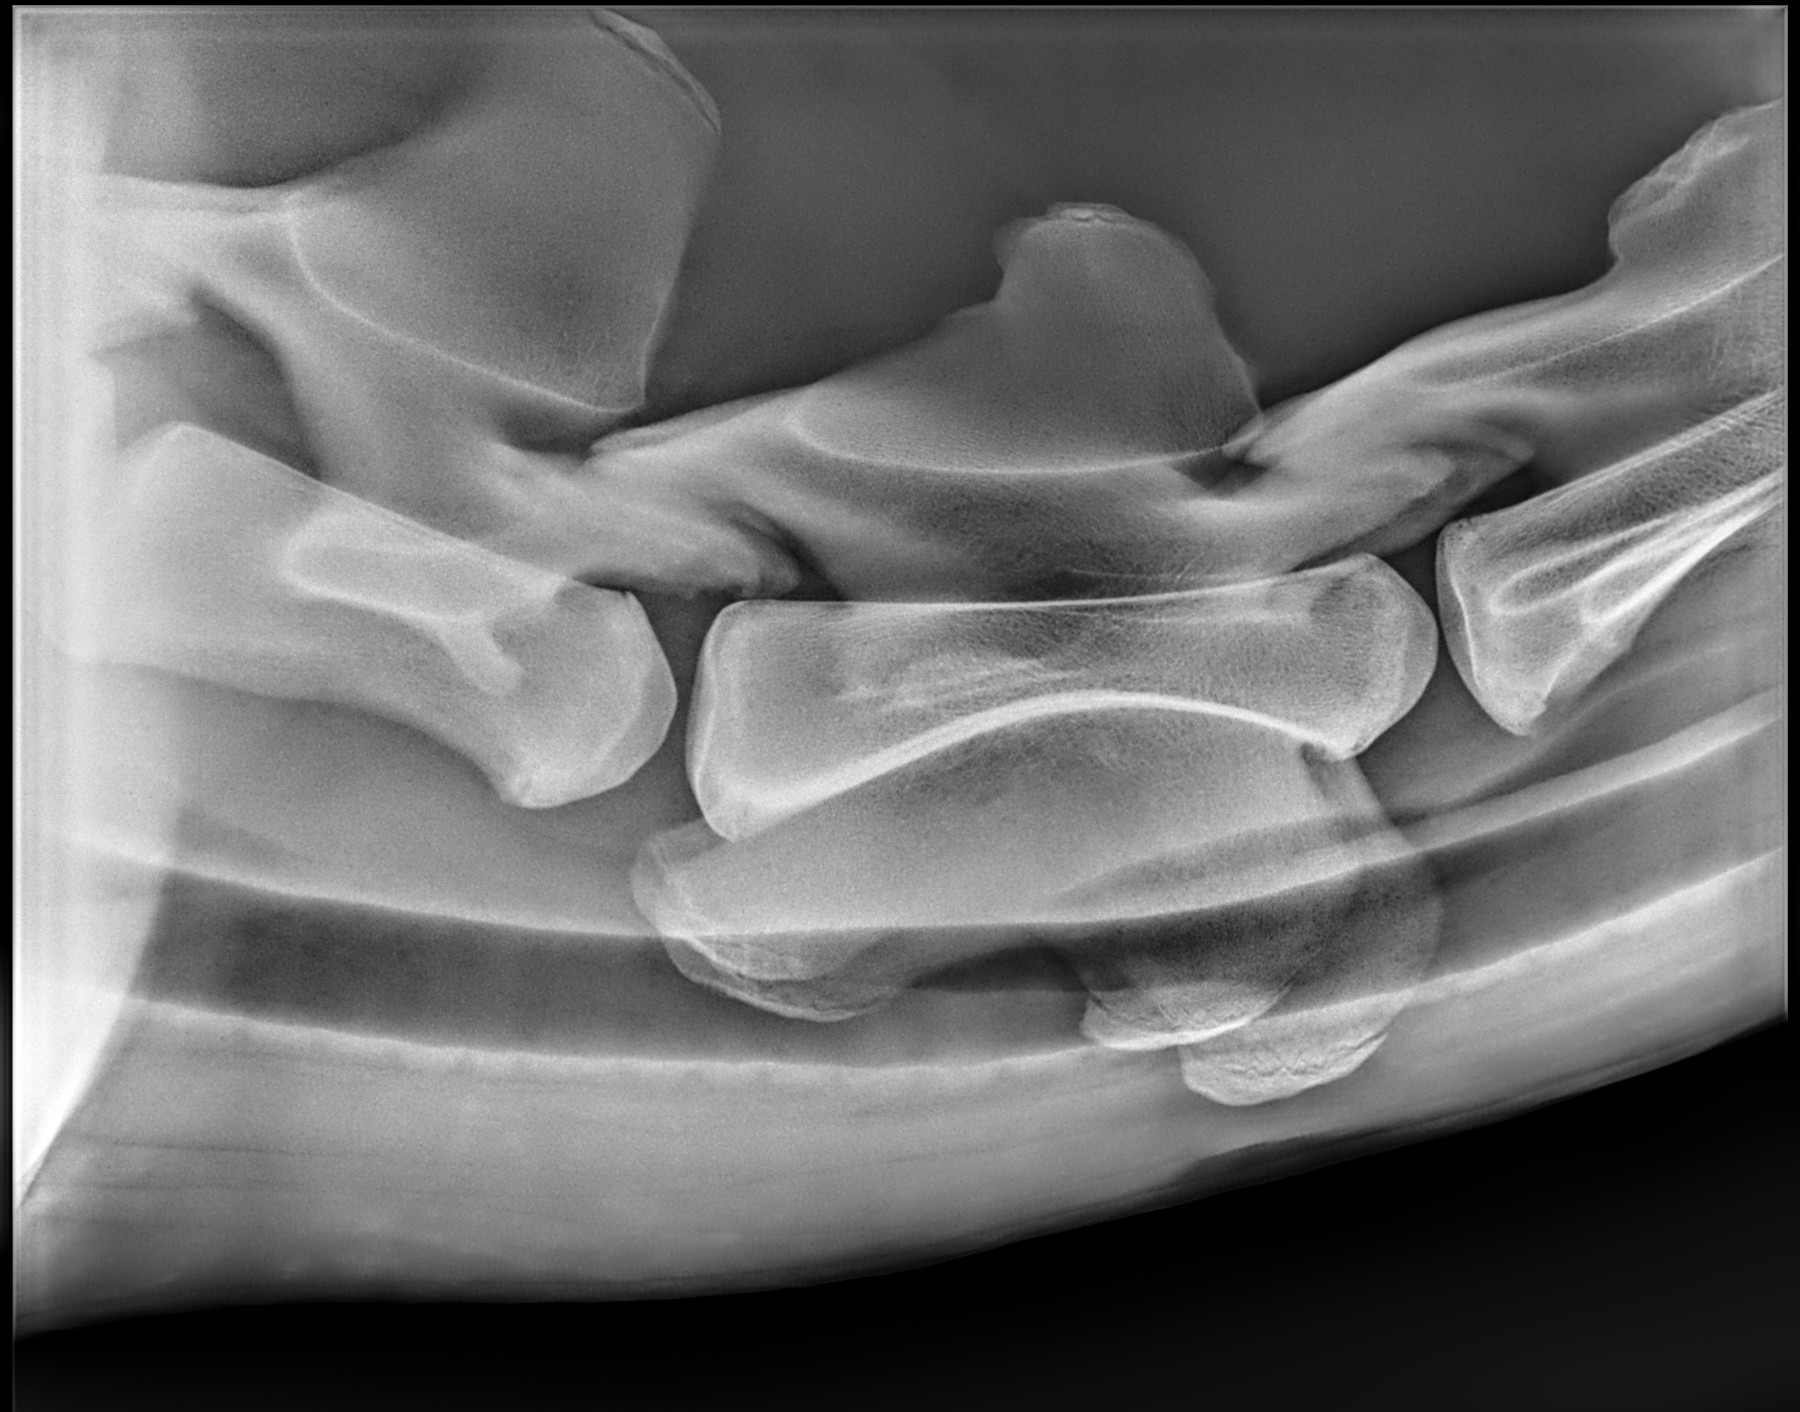

Radiología Digital como Herramienta Complementaria en el Dictamen de Bienes Muebles

Los caballos de salto, en competencia, pueden derribar obstáculos y lastimarse. Si se golpean, no siempre claudican. Considerando al calor como un signo de inflamación, se evaluaron los cambios térmicos de 6 áreas de las extremidades torácicas y pelvianas de 23 caballos de salto en nivel de competencia de 1.05 a 1.60 m de altura, por medio de termografía durante 4 días de competencia (N=2208 áreas).